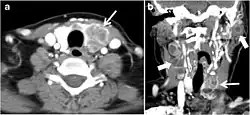

The radiologist must evaluate the central structures draping the thyroid gland including the trachea, oesophagus, larynx, and pharynx, as well as the recurrent laryngeal nerve. Invasion is suspected if the thyroid mass abuts the airway or oesophagus for more than 180 degrees. Luminal deformity, mucosal thickening and mucosal focal irregularity are more specific indicators of invasion. Obliteration of the fat planes of the tracheoesophageal groove in three axial images and signs of vocal cord paralysis are indicative of recurrent laryngeal nerve invasion. Invasion of these central structures meets the criteria for T4a disease (Figs. 5 and and6)6).[1]

Arterial invasion constitutes T4b disease, which may preclude curative surgery. More than 180 degrees of arterial encasement is suggestive of invasion, however, arterial deformity or narrowing is much more suspicious for invasion. The carotid artery is the most commonly involved artery; however, the mediastinal vessels should also be examined. Encasement of the carotid artery or mediastinal vessels for more than 270 degrees is unlikely to be resectable. On the other hand, occlusion or effacement of the internal jugular vein can occur without invasion and does not influence surgical resectability or staging. Asymmetry of the strap muscle and the tumour abutting its external surface are signs of an invasion. However, invasion of the pre-vertebral musculature is more challenging, as a large lesion can compress the muscle without invasion (Figs. 5 and and6)6).[1]

Fig. 6. A 61-year-old female patient with locally aggressive PTC. an Enhanced axial CT scan of the neck demonstrates a heterogeneous infiltrative thyroid mass. This mass diffusely involves the entire gland and circumferentially encases the trachea with involvement of bilateral tracheoesophageal grooves (white arrows). b, c Additional axial cranial images show right cricoid cartilage destruction (black arrows in b), right thyroid cartilage destruction (black arrow in c), right vocal cord paralysis (white arrows in b), and bilateral cervical lymphadenopathy (arrowheads).[1]